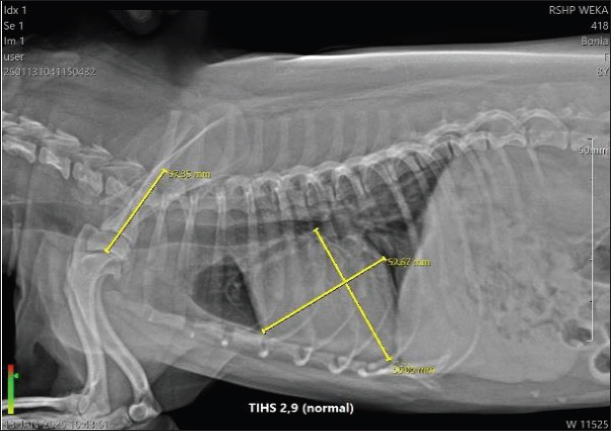

Figure 1 shows the VHS measurement of Bonia’s heart, with a value of 11.2 V, whereas the normal range in dogs is 9.5–10.5 V. This indicates that Bonia is experiencing cardiomegaly. Figure 2 shows the TIHS, a method used to detect MMVD. Under normal conditions, the TIHS value is less than 3 (Marbela et al., 2023); therefore, Bonia is not affected by MMVD.

Fig. 2. Thoracic Inlet heart size (THIS) 2,9 of Bonia.

Table 1 shows that each patient presented with different clinical signs and laboratory results. In Table 2, Bonia was reported with hypotension (77/35 mmHg) and a VHS value of 11.2 V, which falls into the cardiomegaly category. The THIS score was 2.9, indicating no evidence of MMVD because the normal THIS value for dogs is below 3 (Lam et al., 2021). Echocardiography in B-mode showed normal valve movement and valve structure, whereas M-mode measurements were within the normal range. However, color Doppler examination revealed turbulence, suggesting disturbed blood flow and valvular regurgitation. Color Doppler function is used to detect congenital or acquired cardiac diseases (Wess et al., 2021). According to the cardiac biomarkers presented in Table 3, Bonia had NT-proBNP levels of 0.5 ng/ml and cTnI levels <0.1 ng/ml. These values are within the normal range, indicating no myocardial damage or cardiac injury.